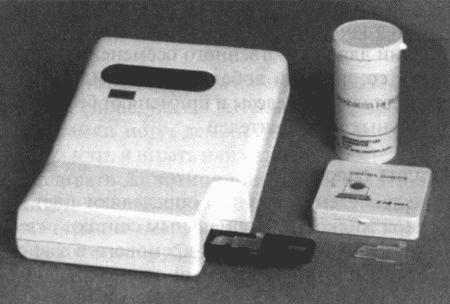

В зависимости от метода исследования (радиоиммунный или иммуноферментный) возможны некоторые расхождения в показателях концентрации прогестерона; при этом следует учитывать, что иммуноферментный метод дает завышенные, но в остальном надежные результаты. Большая часть опубликованных данных (включая данные, приведенные в настоящей главе) получены с помощью радиоиммунного метода. Готовые иммуноферментные тест-системы, предназначенные для определения концентрации прогестерона в плазме крови на различных стадиях эстрального цикла, дают результаты, почти вдвое превосходящие данные радиоимунного анализа (РИА), но в той же степени отражающие характерные циклические изменения. С помощью готовых наборов нельзя получить абсолютные показатели концентрации прогестерона, но можно проследить относительные изменения его концентрации от начала проэструса и до конца цикла.

Фиг. 1.3.

Эндоскопическое исследование слизистой влагалища. Динамика изменений на протяжении цикла: (а) проэтрус — розовая окраска и отечность; (b) начало эструса — слизистая бледнеет, отек начинает уменьшаться (обычно перед пиком ЛГ); (c) середина эструса — слизистая бледная, уменьшение отека (сморщивание) явно выражено, что соответствует середине фертильного периода; (d) начало метэструса — видны закругленные складки, при прикосновении слизистая смыкается, образуя розетку (е) (см. Приложение)

Прогестерон является единственным гормоном, концентрацию которого используют как ориентир при вычислении фертильного периода. Хотя ЛГ и эстрадиол в этом отношении даже более информативны, их определение не практикуется.